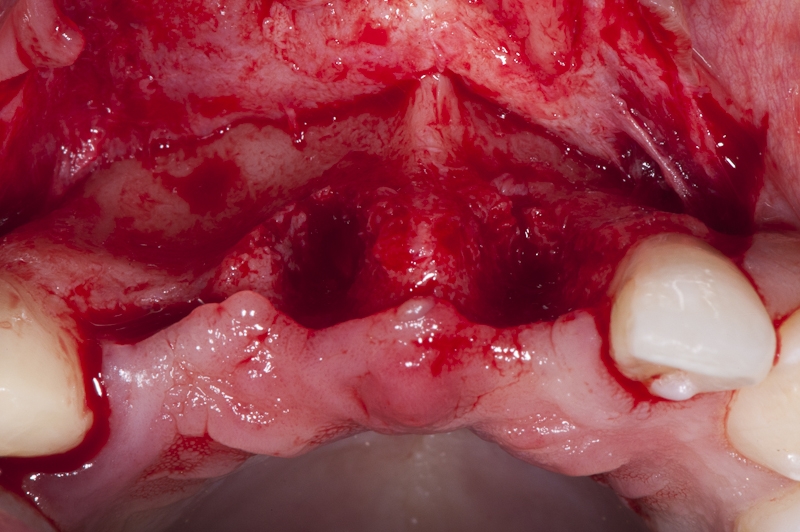

04/17 - Full flap elevation and severe hard tissue exposure